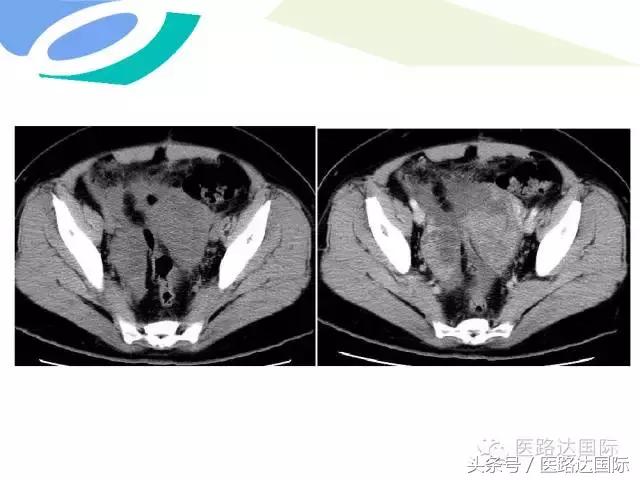

女性生殖系统结核的影像诊断及鉴别